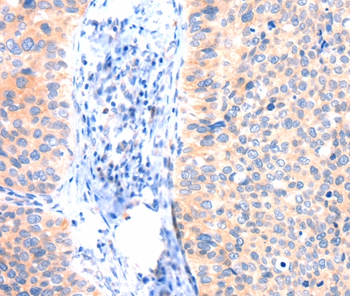

The image on the left is immunohistochemistry of paraffin-embedded Human cervical cancer tissue using CSB-PA981926(ANK3 Antibody) at dilution 1/50, on the right is treated with synthetic peptide. (Original magnification: x200)